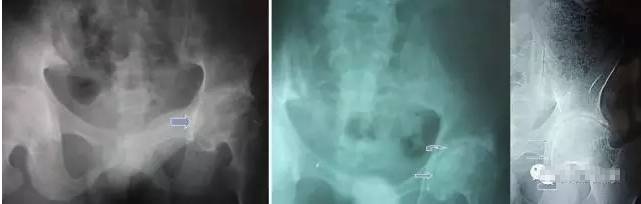

男,25岁,跌伤至右髋关节强直8年,左髋关节功能正常,右髋关节无功能,髋关节X光正位片显示:左髋关节间隙正常,右髋关节3/5骨性融合,仅关节上缘未融合,关节后下边缘增生,股骨头表面粗糙。

诊断:外伤性右髋关节强直